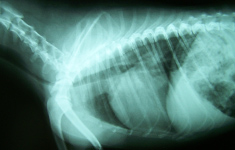

radiologia é definida como a parte da ciência que estuda os órgãos e estruturas internas do corpo com o auxílio de equipamentos que emitem feixes de radiação para formar imagens. Existem, até mesmo na veterinária, diversas técnicas, dentre elas umas mais atuais e outras mais específicas para cada situação.

O diagnóstico por imagem é de extrema importância, uma vez que um bom profissional veterinário, não é aquele que bate o olho no animal e o diagnostica, e sim aquele que faz um bom exame clínico, e a partir do que o animal e o dono o apresentam, sabe exatamente como prosseguir com os exames complementares (laboratoriais, histológicos, de imagem, etc.) que estão a sua disposição e auxiliarão a fechar um diagnóstico correto e seguro. Por se tratar da visualização de estruturas não visíveis a olho nu, geralmente, esse tipo de exame, na Medicina Veterinária, é utilizado para determinações clínicas, e principalmente, cirurgias.